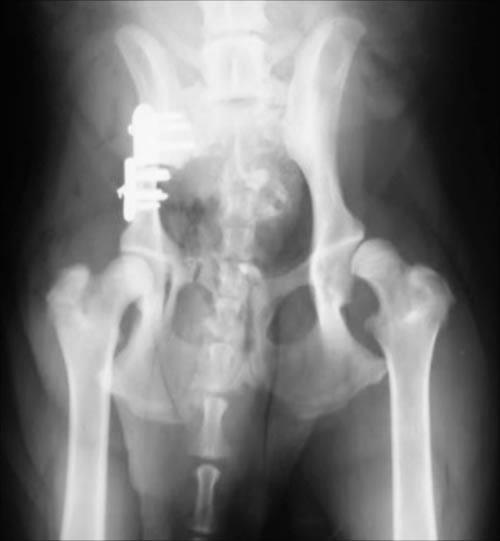

DPO(Double Pelvic Osteotomy)/ 二点骨盤骨切り術

TPO(Triple Pelvic Osteotomy)/ 三点骨盤骨切り術

5カ月齢~8カ月齢までの症例で有効な手術。腸骨・恥骨の二点もしくは腸骨・恥骨・坐骨の三点に骨切りをおこない、寛骨臼による大腿骨頭のカバーがよくなるよう腸骨を外側へ回転させる術式です